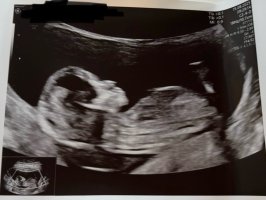

Tipper jente!Noen som kan hjelpe venninna mi med denne?

Gutt tipper jeg, syntes NUB er veldig skråNoen som kan hjelpe venninna mi med denne?